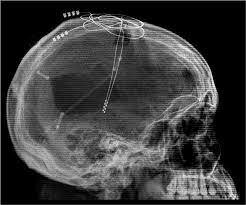

J. Lawrence Pool

Neurocirujano de la Universidad de Columbia, describió por primera vez el uso de electrodos implantados subcorticalmente para la estimulación crónica terapéutica. Este reportó “resultados favorables” durante las primeras semanas tras implantar un electrodo en la cabeza de núcleo caudado de una mujer con depresión y anorexia (Barroso, 2021)

• José Manuel Rodríguez Delgado

José Manuel Rodríguez Delgado

Crea el programa de estimulación crónica de estructuras cerebrales profundas en pacientes con enfermedades psiquiátricas. Inventó el “stimoceiver”, un dispositivo que implantado en el cerebro permitía dirigir la conducta de organismos biológicos a distancia mediante estímulos eléctricos en determinadas partes del cerebro. Se creyò que fuese posible el control y la manipulación de la mente humana a través de la tecnología para así condicionar su comportamiento (Barroso, 2021)

Inició su trabajo encaminado en crear implantes cerebrales que imitan a las neuronas que intervienen en la memoria a largo plazo. Los implantes cerebrales se ven como una gran esperanza para tratar pacientes de Alzheimer o con derrames cerebrales. Sus estudios se ejecutaron inicialmente con ratones para luego ser probados en monos por medio de electrodos puede procesar la información igual que lo hacen las neuronas reales. (Cohen, 2013)